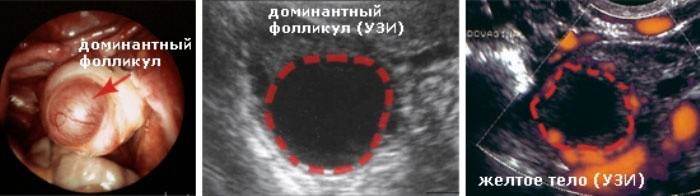

Ultrazvukové vyšetrenie

Metóda ultrazvukovej diagnostiky sa považuje za najpresnejšiu pri určovaní ovulácie. Keď sa žena rozhodla podstúpiť takýto postup, mala by pochopiť, že to nebude obmedzené na jeden deň. Je potrebné vyšetriť sa v strede cyklu niekoľko dní v rade, aby sa zistilo, ako sa dominantný folikul mení a rast. Bezprostredne pred ovuláciou sa na ňom vytvorí malý tuber s vajíčkom. A folikul, ktorý dovtedy dosiahol priemer 2 až 3 cm v priemere, a samotný tubercle je jasne viditeľný na ultrazvukovom prístroji.

Po prasknutí dominantného folikulu opúšťa vajíčko žena brucho a mizne, na tomto mieste vidíme iba luteum corpus a za maternicou sa z neho uvoľní malé množstvo tekutiny. Ak sa ultrazvuková diagnostika vykonáva denne uprostred cyklu, tieto zmeny sa určite zaznamenajú a nebude ťažké vypočítať deň nástupu ovulácie.